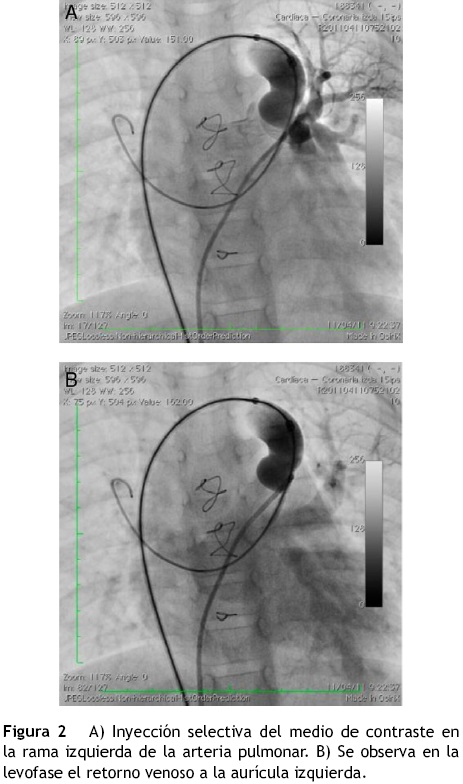

Se realizó cateterismo bajo anestesia general, en donde se evidenció la vena vertical con una medida en su porción superior de 12 mm, en su porción más estrecha de 9mm y en su porción distal de 10 mm (fig. 1).

Se realizó el procedimiento avanzando una guía Amplatz extra stiff (Cook Medical, EE. UU.) a través de la vena cava inferior, aurícula derecha, vena cava superior, vena braquicefálica, vena vertical, aurícula izquierda y vena pulmonar superior izquierda. Se hizo oclusión con balón a nivel de la vena vertical y se realizó una inyección selectiva en la rama izquierda de la arteria pulmonar, observando en la levofase un adecuado retorno de las venas pulmonares a la aurícula izquierda (fig. 2A y B). Sobre la guía se avanzó un sistema de liberación de Amplatzer® 8 Fy a través de este se depositó un AVP de 16 mm en la vena vertical para su oclusión. Durante el procedimiento se administraron 50 U/kg de heparina.